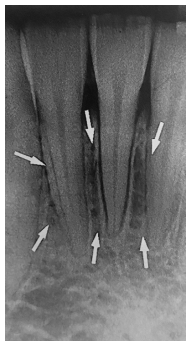

As estruturas anatômicas apontada pelas setas brancas correspondem à(ao)